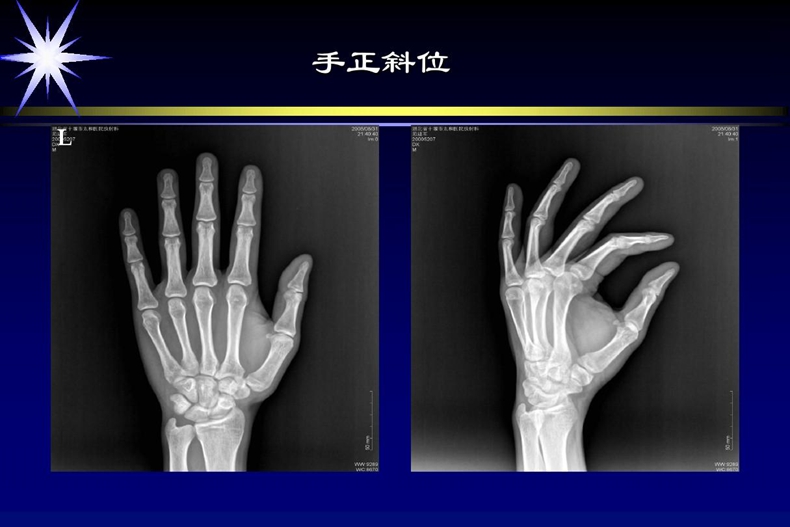

3、放射科医生

7、放射科技师